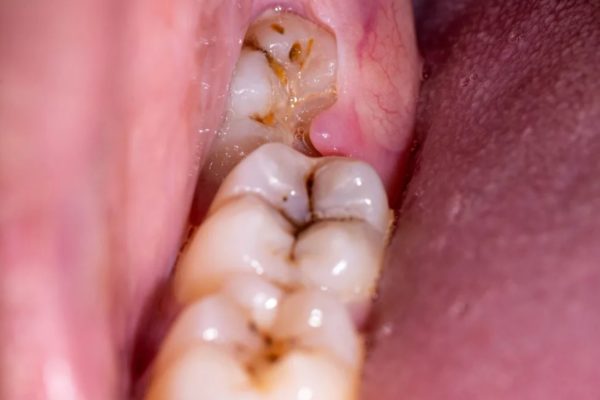

Hiện tượng mọc răng khôn bị sưng lợi trùm là gì? Khi răng khôn bắt đầu mọc, nhiều người cảm thấy đau, nhức và sưng ở vùng hàm sau. Một trong những tình trạng phổ biến ...